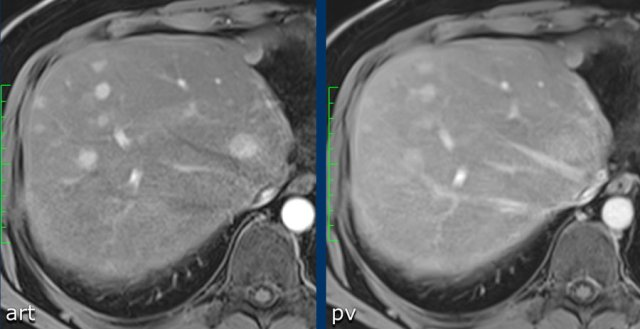

MRI-images of the same patient.

The enhancement of this lesion follows the enhancement of the blood pool.